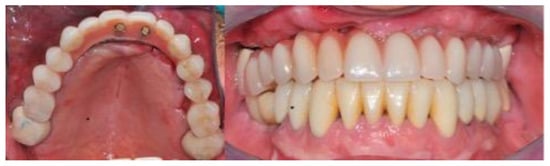

Not less than six months after CBR, a CBCT was scanned for all the patients (T1) to control the outcomes of the surgery after the graft healing phase (6–12 months) (Figure 4 and Figure 5).

Figure 4.

This composite resumes the surgical workflow from the custom Ti Mesh graft healing to the implant placement. In the CBCT (T1) screenshots it is possible to appreciate the bone volume gain. From the top left clockwise: starting situation, grid removal after 6 months; section of CBCT shows the bone volume gain, occlusal view just before implant surgery.

Figure 5.

Intra oral radiograph before and after implant placement. Left: intra-oral X-ray after grid removal and healing occurred. Right: fixture installation.